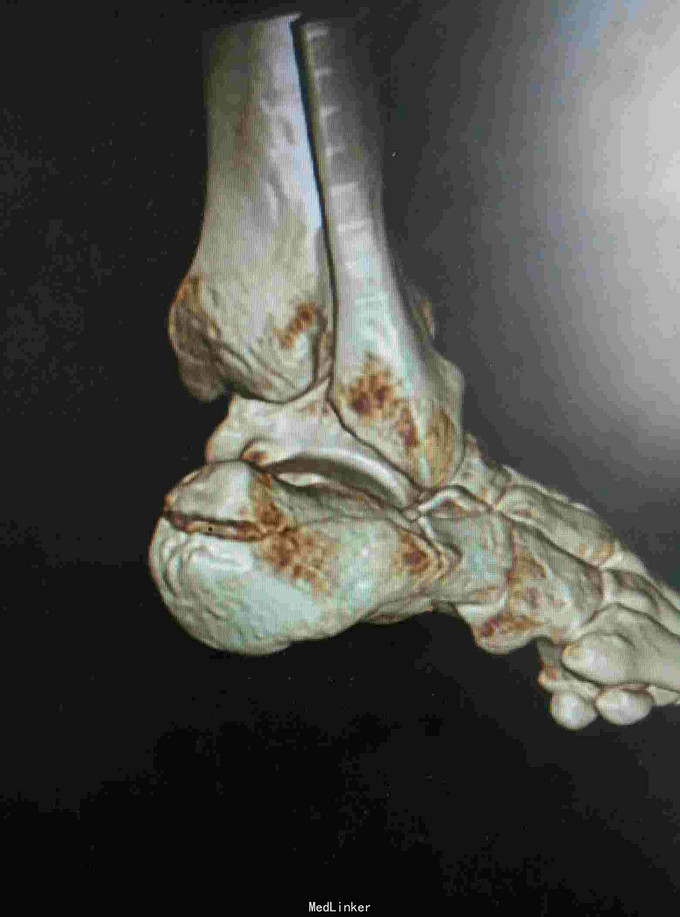

右足跟部肿痛,活动受限2小时 患者因高处坠落右足跟着地,当即出现右足跟肿痛,活动受限,余未诉特殊不适。急诊入院摄片提示跟骨骨折。

查体:脊柱生理弯曲存在,骨盆挤压分离实验阴性,双上肢肌力、活动正常,左下肢肌力、活动正常,右膝活动无明显异常,右足跟肿胀明显,无张力性水泡,皮下淤青,右踝关节活动稍受限。 辅查:平片及CT提示右跟骨粉碎性骨折

诊断:右跟骨粉碎性骨折 治疗:骨折切开复位内固定